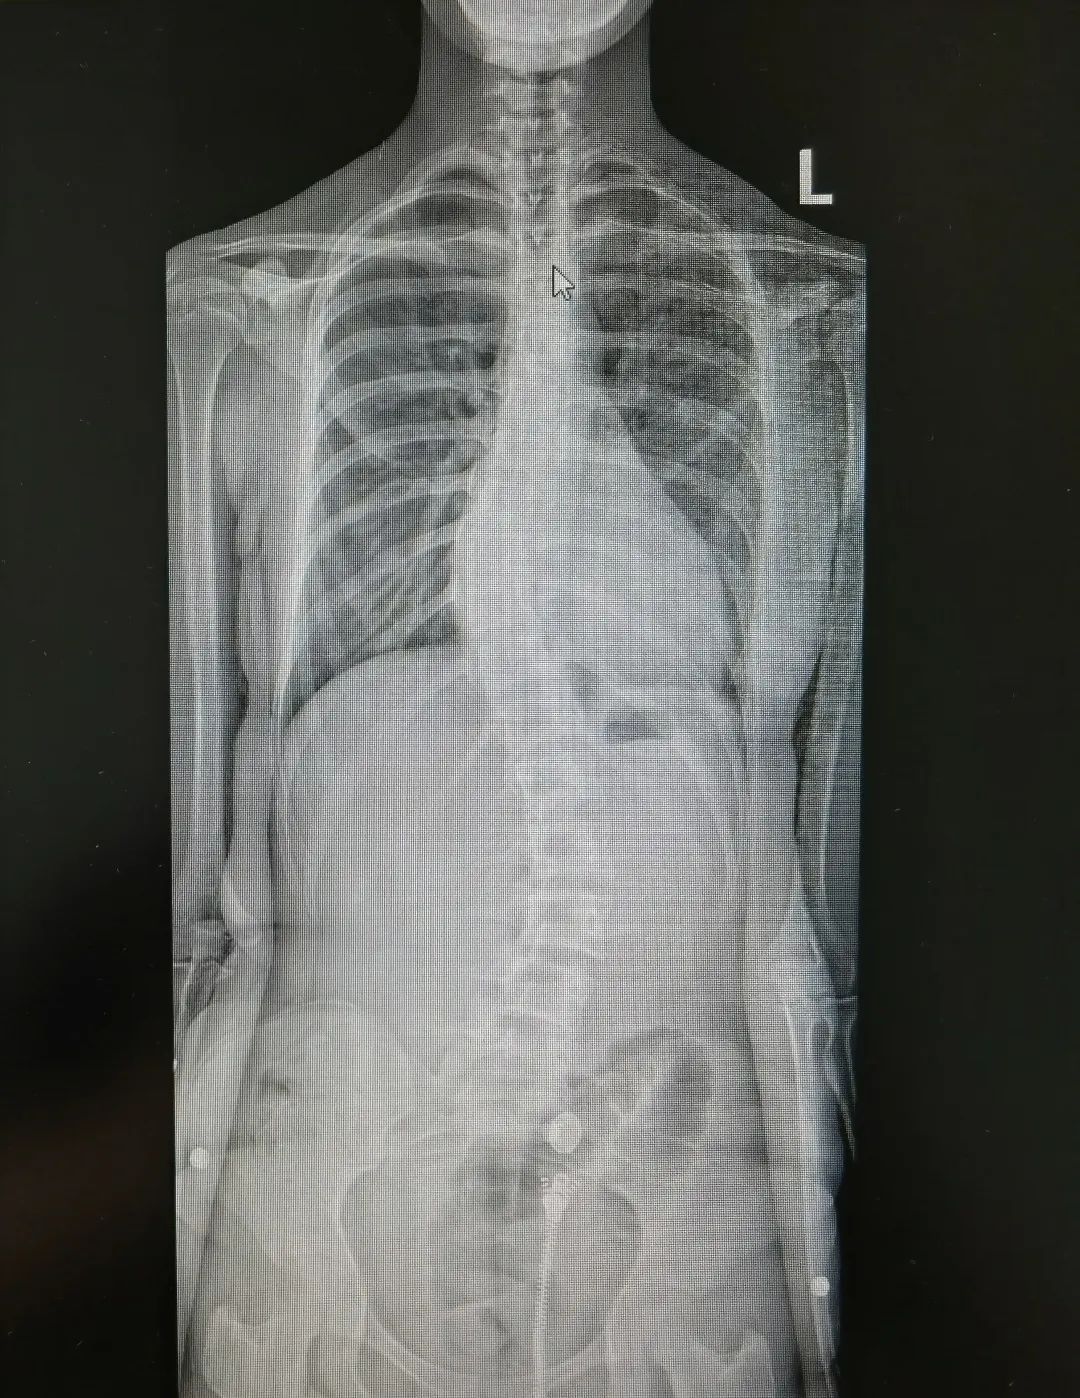

神经肌肉性脊柱侧弯术前术后图

除了以上三类,还有一类名为神经肌肉性脊柱侧弯。这一类病人在发现脊柱侧弯前就已患有神经和肌肉疾病。一旦疾病引起肌肉力量失衡,脊柱会失去支撑点,就会发生脊柱侧弯。

躺在床上12岁女孩玲玲(化名)就是一名神经纤维瘤病患儿。玲玲文静懂事,小的时候为了治这个病,她的头上、肚子上都挨了好几刀。但是纤维瘤长得实在太多,医生只能尽力切除。三年前,奶奶发现孩子脊柱也不对劲,一查果然是脊柱侧弯。年迈的奶奶看着玲玲一天天长大,想要给孩子尽量健康的身体,下定决心带她做手术。

“在这20例的手术里,这个孩子的情况相对特殊,手术难度也比较高。”陈文昊副主任说,“孩子的脊柱侧弯已经达到85°,基本上已经成为一个直角,只能通过手术矫正,如果不手术,这一类型的脊柱侧弯进展会非常快。”

但因为长期生病,玲玲的骨密度非常低,小小年纪已经骨质疏松——她的骨头像70、80岁的老人一样。在弯的最厉害的地方,骨头中根极其纤细,甚至没有,根本打不进钉子。同时神经纤维瘤病的孩子脊髓对矫形的耐受能力较差,为了不影响玲玲的神经和肌力,手术中陈文昊副主任只能降低矫形强度。

克服种种不利因素,手术基本达到了既定的矫正效果,命运坎坷的玲玲在日后也能像其他孩子一样抬头挺胸。